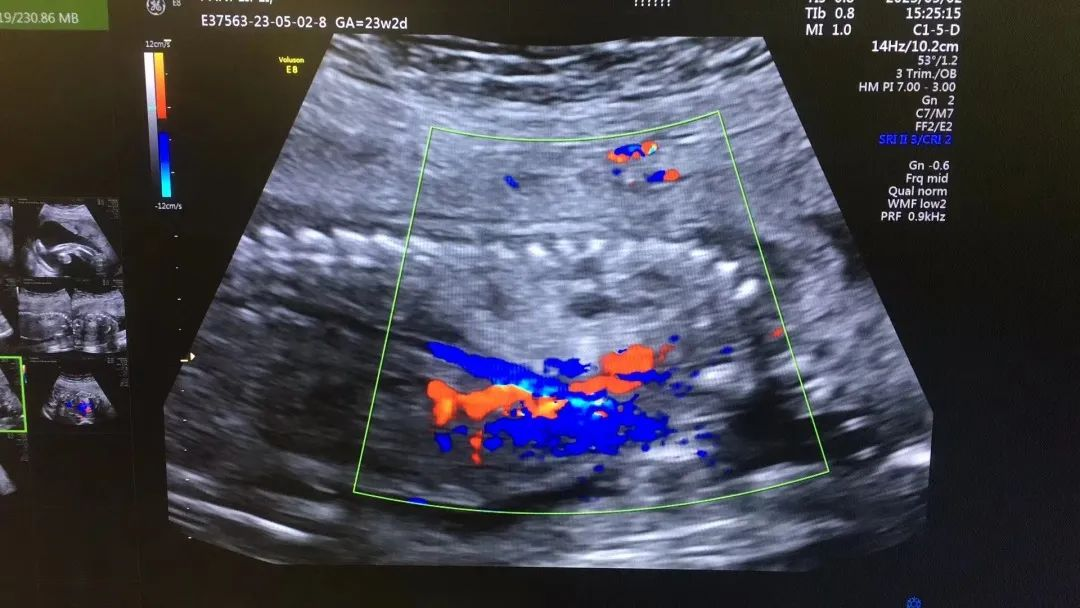

武漢的劉女士(化名),前幾個(gè)月剛懷上寶寶,全家都特別高興。懷孕23周+時(shí),劉女士在家人的陪伴下來(lái)到武漢仁愛(ài)醫(yī)院超聲科做了四維彩超檢查,當(dāng)醫(yī)生拿出檢查報(bào)告的時(shí)候,劉女士卻當(dāng)場(chǎng)傻眼了,原來(lái),在四維彩超的報(bào)告里,診斷出了胎兒右肺囊性腺瘤樣病變,她的心頓時(shí)揪了起來(lái)!

劉女士看到檢查結(jié)果后,擔(dān)心該病變會(huì)影響腹中寶寶的健康,考慮是否應(yīng)該終止妊娠。隨即,武漢仁愛(ài)醫(yī)院超聲科王娟主任為劉女士耐心地解釋?zhuān)骸跋忍煨苑文蚁倭鍪且环N肺組織錯(cuò)構(gòu)畸形,先天性肺囊腺瘤畸形病例約70%的腫塊大小較穩(wěn)定;約20%腫塊產(chǎn)前明顯縮小或消失;僅10%腫塊是進(jìn)行性增大。單純的先天性肺囊腺瘤(CCAM)無(wú)水腫的胎兒可以密切隨訪,在28周前接受連續(xù)超聲復(fù)查,CVR<1.6,一般超聲動(dòng)態(tài)監(jiān)測(cè)2~4周監(jiān)測(cè)一次,而對(duì)于CVR≥1.6的需要在28周前每周1-2次的超聲監(jiān)測(cè),防止出現(xiàn)胎兒水腫,直到分娩?!?/p>